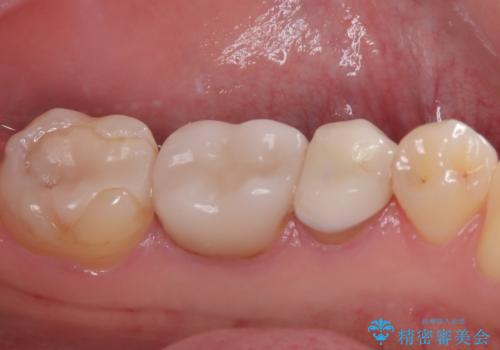

左下奥歯は詰め物と周辺の歯が欠けて、しみている状態でした。

部分的な詰め物ですと、再度破損リスクが高いため、高強度のセラミッククラウンにて補綴治療を行うこととしました。

また、親知らずが埋もれており、よい機会なので抜歯を行ってからセラミッククラウンを装着することとしました。